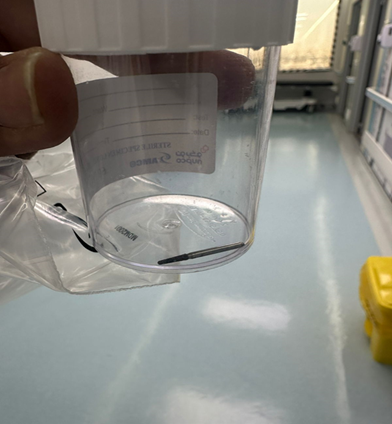

Figure 5: Revealed FB after the exit from the GI.